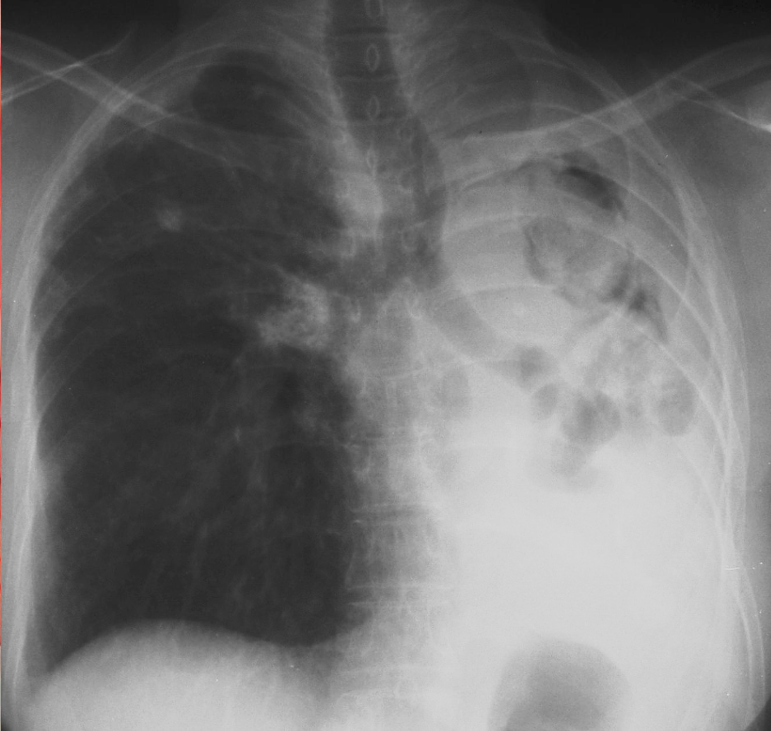

What is this ?

Chronic cavitary pulmonary aspergillosis

-left apical cavity due to CCA

-In CCA, the cavity exists first, aspergiloma grows, cavity expands through damage n inflammation n stuff

-roling fungal balls cann cause problems

-other lung evebtually fibroses